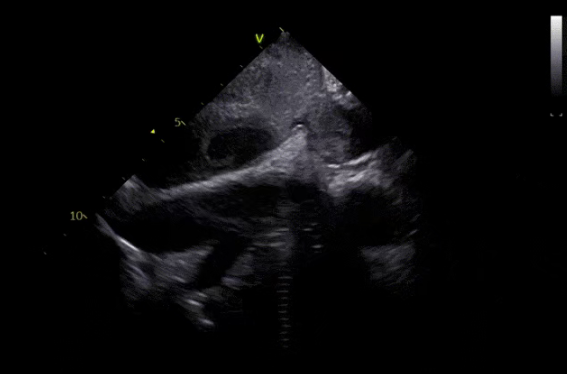

ICE扫描心耳评估血栓位置

渐进式将血栓推行远端